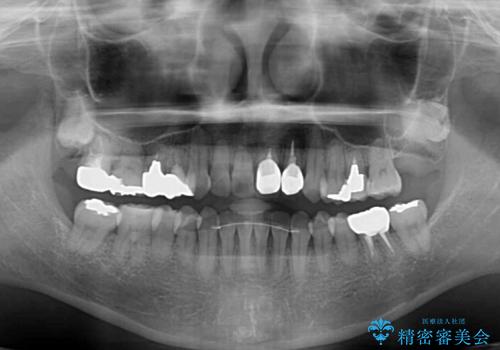

骨格的に下顎が前方位にありますが、歯列矯正で前歯の被蓋関係を改善することができると判断されたため、インビザラインにより矯正治療を行うこととしました。

また、上顎前歯と下顎大臼歯に神経を取り除いた歯があったため、矯正治療後に、セラミッククラウンにて補綴することとしました。

前歯が内側に倒れ込む力がかかり、正常な歯ぎしりもできないため、非常に負担のかかりやすい咬み合わせでした。

矯正治療中に上顎前歯が下顎前歯を乗り越える際は、前歯でしか咬めない状況が続くため、食事など不便を感じましたが、治療後には前歯の痛みもなくなり、安定した咬み合わせとなりました。